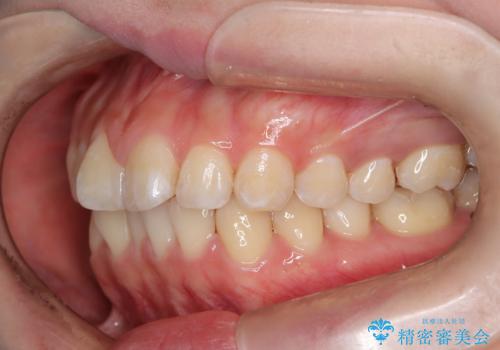

- 口元の突出感、歯のがたつきを主訴に来院された患者様です。非抜歯にて口元を下げるような治療計画を立案しました。非常に治療に対して真面目で協力的な患者様で、一緒に理想形を相談しながら治療を進めました。矯正前には、虫歯治療や親知らず抜歯を行っています。噛みしめ癖が強く、終盤は奥歯の噛み合わせのためにゴム掛けにご協力いただきました。